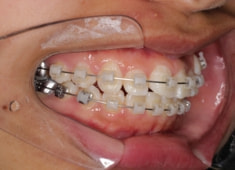

治療開始時